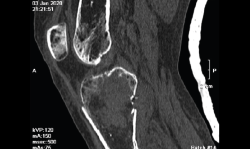

4.3. Osteocondritis

En la osteocondritis se aprecia una lesión subcondral caracterizada por resorción ósea, colapso y la formación de un secuestro.

El estudio por RM es una herramienta valiosa para diagnosticar e identificar las lesiones del cartílago. Conocer el aspecto del cartílago y saber cuánto y cuándo se lesiona, basándose en las clasificaciones actuales, permiten al radiólogo proporcionar la máxima información al clínico(20).

Figura 53. Corte de secuencia sagital (A) y axial (B) T2 Fat-Sat de RM de rodilla: lesiones osteocondrales en el fémur y la rótula.

Numerosos estudios demuestran la utilidad de la RM para definir la estabilidad o inestabilidad de la lesión en la osteocondritis, destacando su carácter no invasivo y la capacidad de valorar la progresión y la respuesta al tratamiento(21)(Figuras 53 y 54).